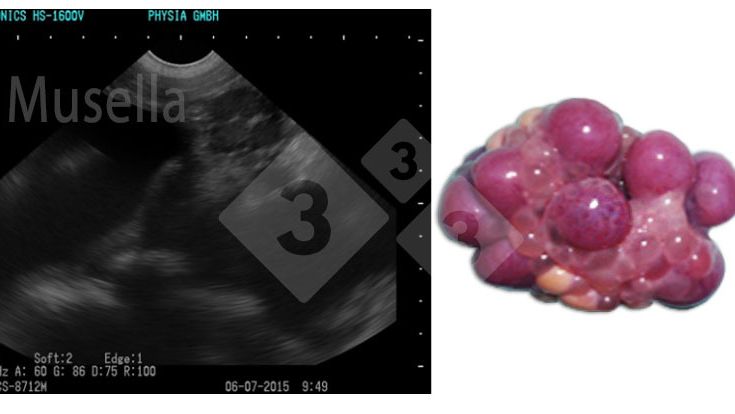

Ecografia di precisione nelle scrofe: Molto più che un controllo di gravidanza!!

L'ecografia può essere utilizzata per visualizzare le strutture ovariche, valutare lo stato puberale e diagnosticare patologie ovariche in scrofe e scrofette....